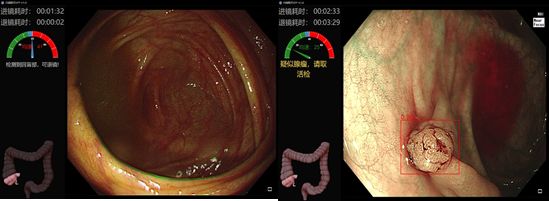

EndoAngel®产品的功能包括上消化道盲区监测、可疑病灶识别,下消化道退镜速度监测、回盲部位识别、息肉识别等。有了EndoAngel®的辅助,有望发现更多的消化道早癌。除以上功能外,我们还在不断追求新的突破,目前已启动研发早癌分化程度和边界预测、食管静脉曲张辅助诊断、实时肠道清洁度评估以及在胆胰EUS和ERCP中的应用。

EndoAngel®下消化道辅助监测(来源:Endoangel公众号)